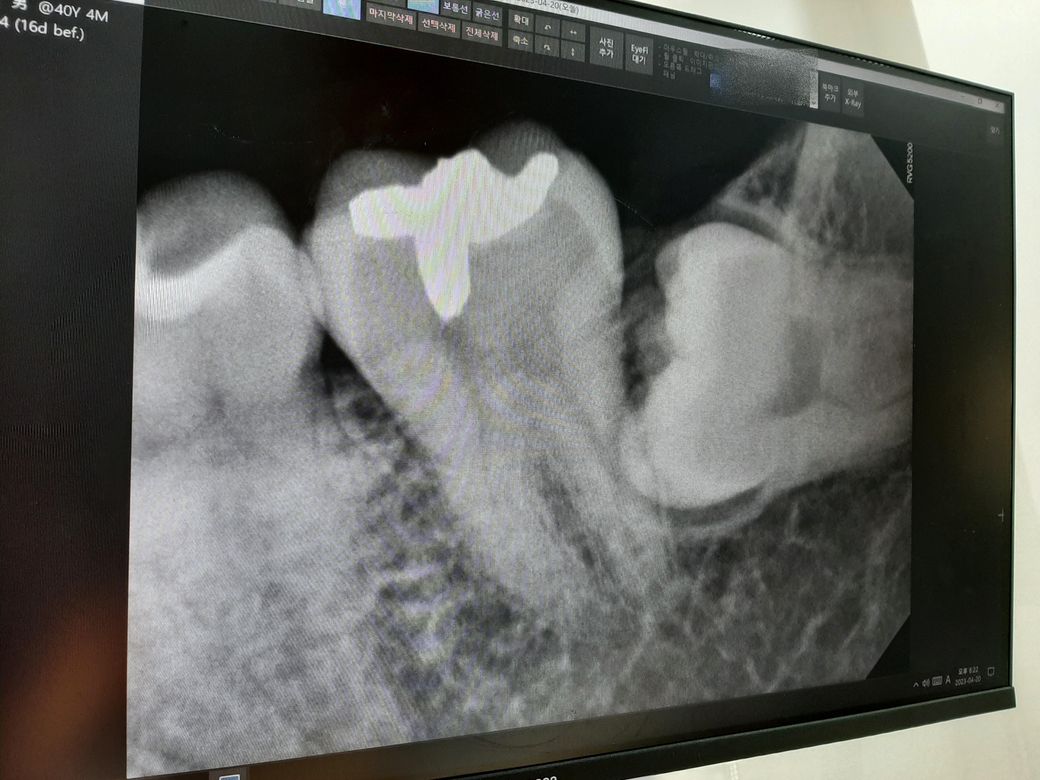

왼쪽 아래 사랑니 사진

1. CT 찍어보니 사랑니에 신경이 지나가서 발치 시 건드릴 수 있다. 그러면 안면마비가 오고 회복이 안 될 수 있다.

2. 왼쪽 사랑니는 잇몸으로 덮여 있고 사진 상으로는 어금니와 사랑니 사이에 충치나 염증이 있어 보이진 않는다.

3. 환자가 지금 사랑니 쪽 통증이라기보단 예방 목적으로 뽑으려는 거라 발치를 권유하진 않는다.